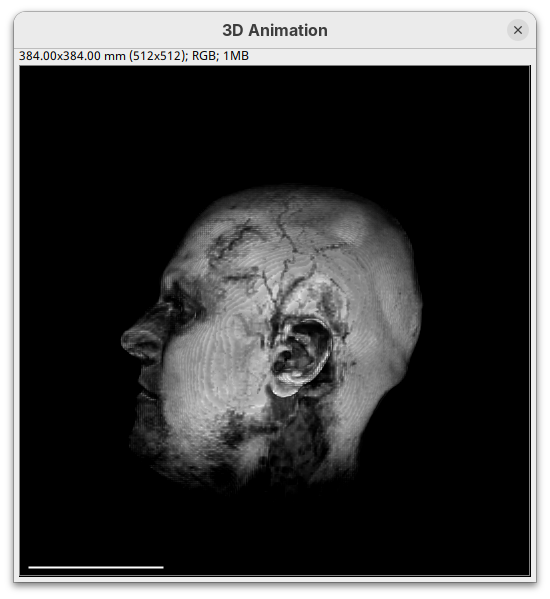

- Change the intensity minimum to

250.

You will see that the darkest parts of the rendering will become even darker and no longer visible. We are losing real information from the data; we do not want that.